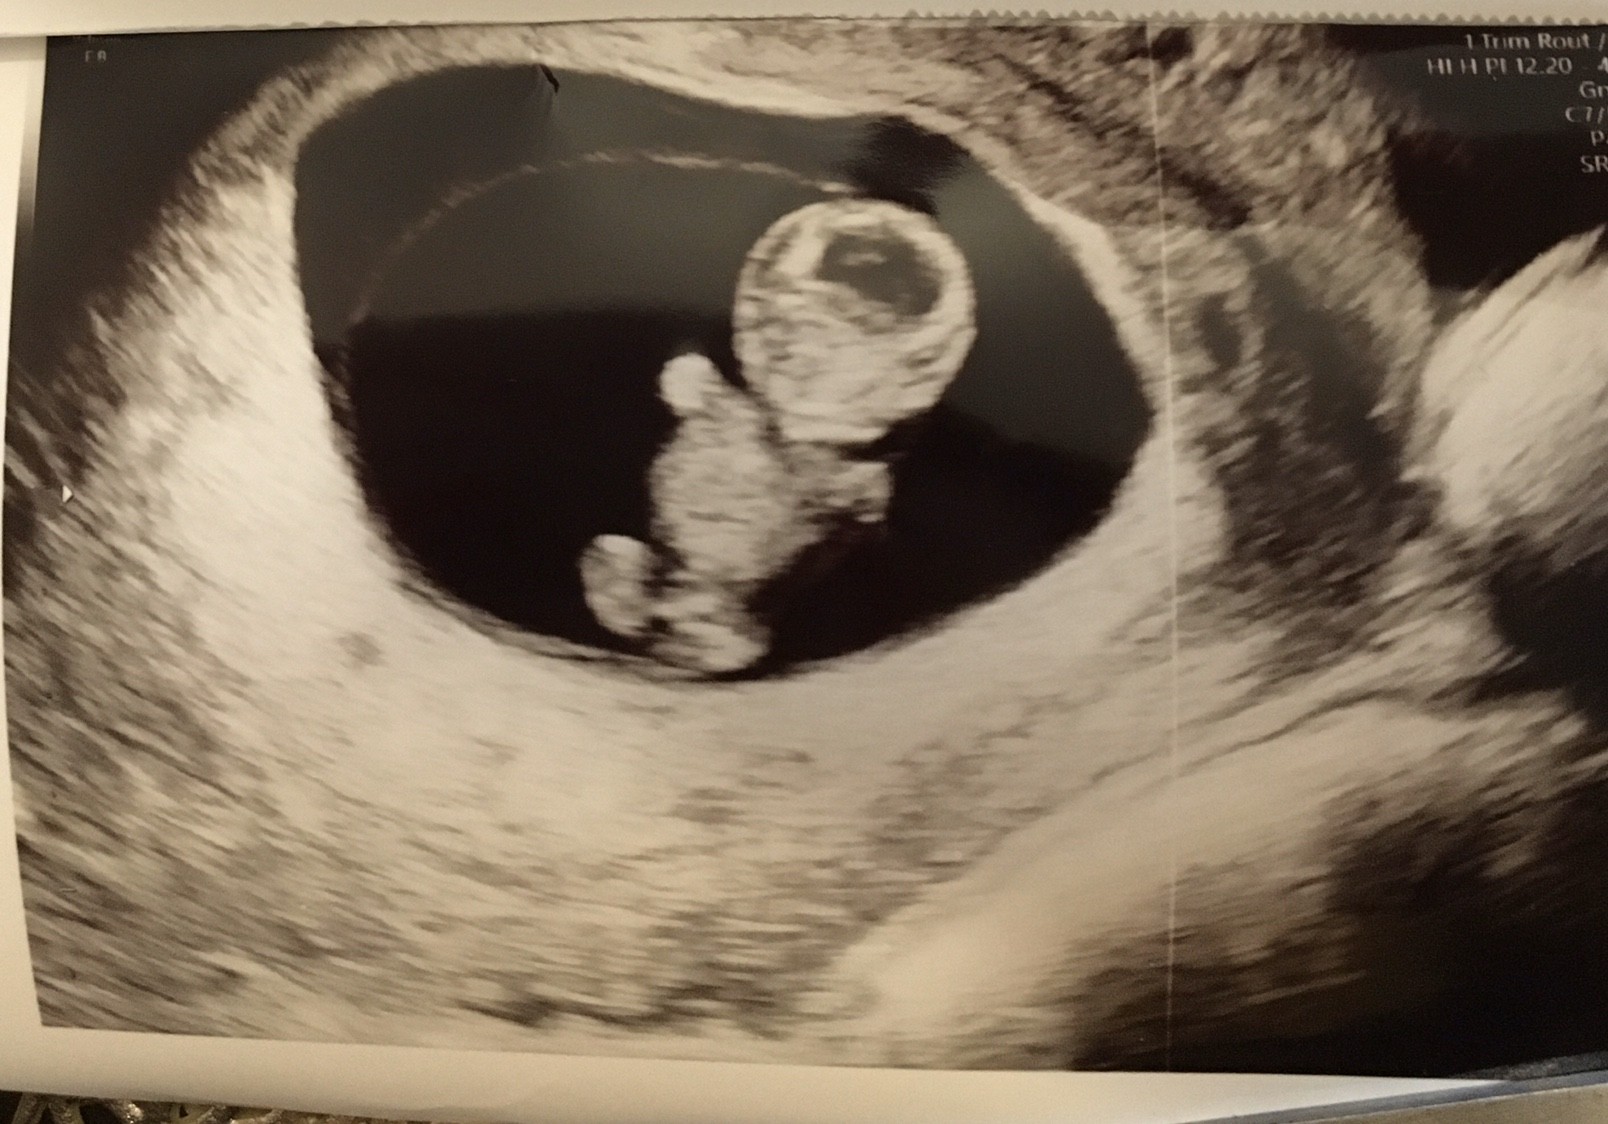

O ja jakie cudo

Urocze zdjęcieElo ciotki![]()

No jakaś modelka albo model się szykujeprzypomina trochę misia Haribo [emoji28]